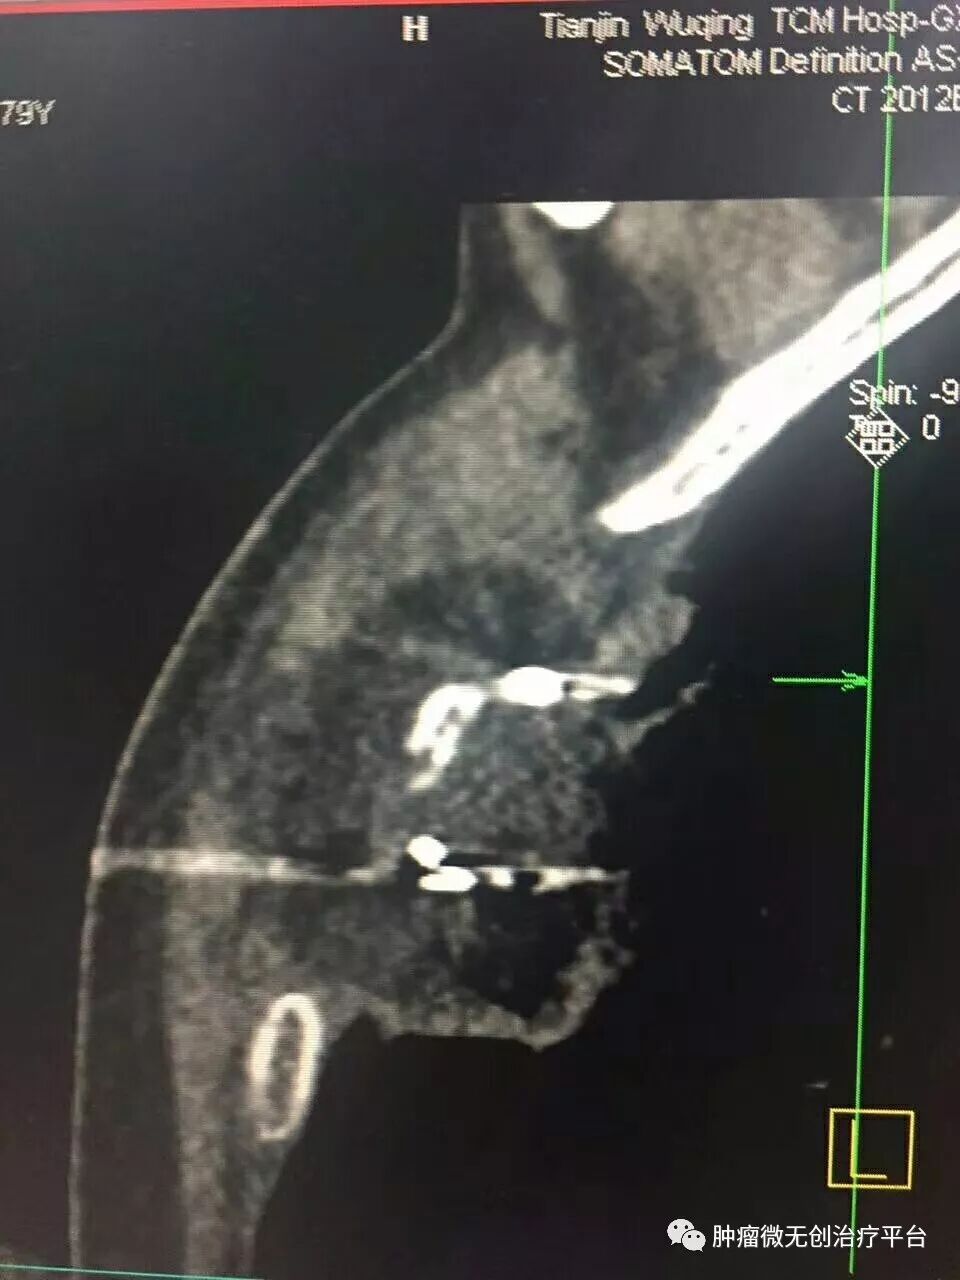

正文:5月28日,右肺腺癌侵犯胸壁患者,在天津市武清区中医医院胸外科进行氩氦刀冷冻消融治疗。

患者情况高龄(79岁)右肺腺癌侵犯胸壁患者肿瘤供血动脉栓塞➕氩氦刀冷冻消融术:图1-2术前PET-CT;图3术前CT;图4-5肿瘤供血动脉栓塞介入;图6-9氩氦刀冷冻消融治疗。